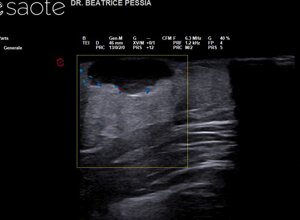

TIROIDE